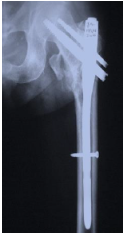

Tipo de fractura de esta radiografia

Subtrocanterica femoral

Mecanismo de lesion de esta fractura

Lesiones de alta energia en jovenes (Trafico, caidas, armas de fuego)

Fracturas patologicas

Lesiones de baja energia (caida de propia altura) en ancianos

Clasificacion de Fielding (para fracturas subtrocantericas de femur)

1. Tipo I → altura del trocánter menor.

2. Tipo II → menos de 2.5 cm por debajo del trocánter menor.

3. Tipo III 2.5 a 5 cm por debajo del trocánter menor.

Tratamiento de esta fractura

Clavo intramedular con pernos de segunda generacion

Implantes si no hay recursos